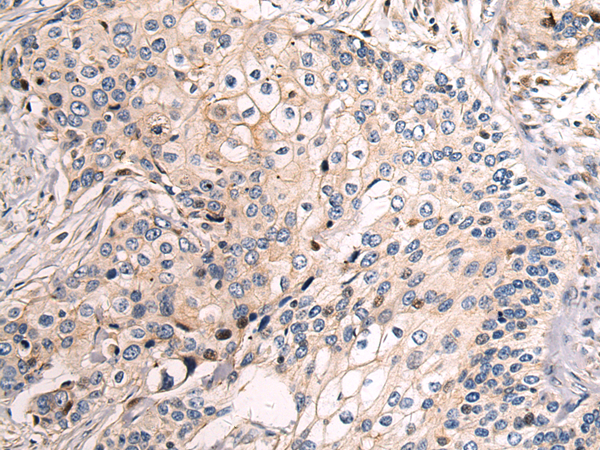

The image is immunohistochemistry of paraffin-embedded Human cervical cancer tissue using P03323(SH3BGR Antibody) at dilution 1/70. (Original magnification: ×200) |